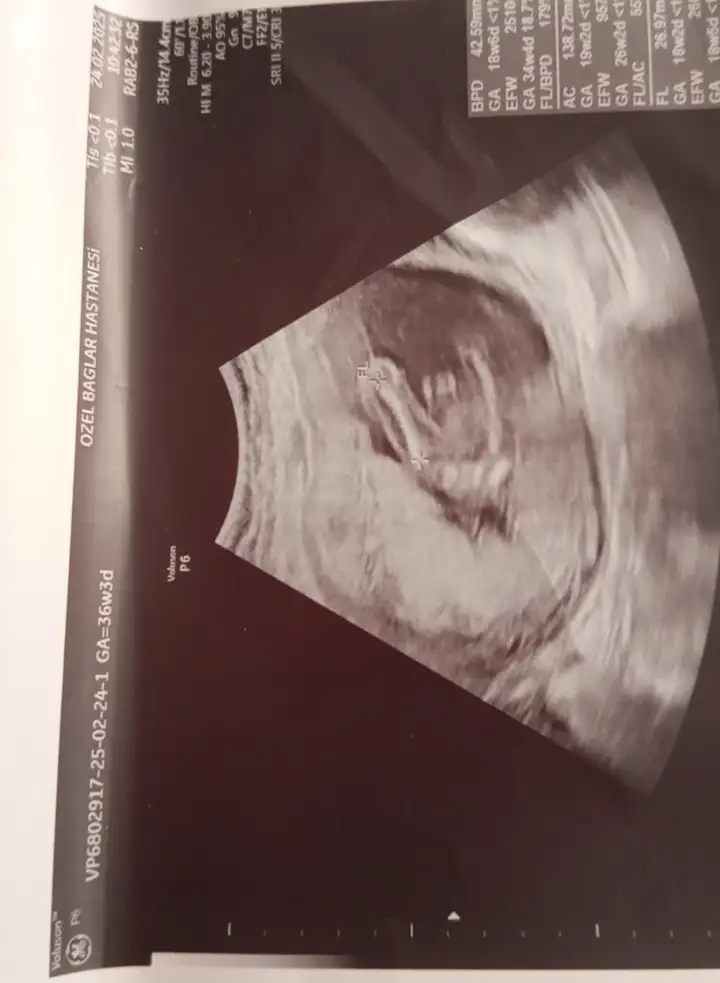

Kızlar ultrason resimlerinizi ve cinsiyetinizi paylaşında nub teorisi tutuyor mu bakalım

Kızlar bebişlerinizin ultrason resimlerini ve cinsiyetini kaçıncı haftada olduklarını yazında kendi ultrason resimlerimizle kıyaslayıp fikirde bulunalım. Nub teorisi, kafa şekli, kemik yapısından cinsiyet teorileri tutuyor mu bakalım bir🥰